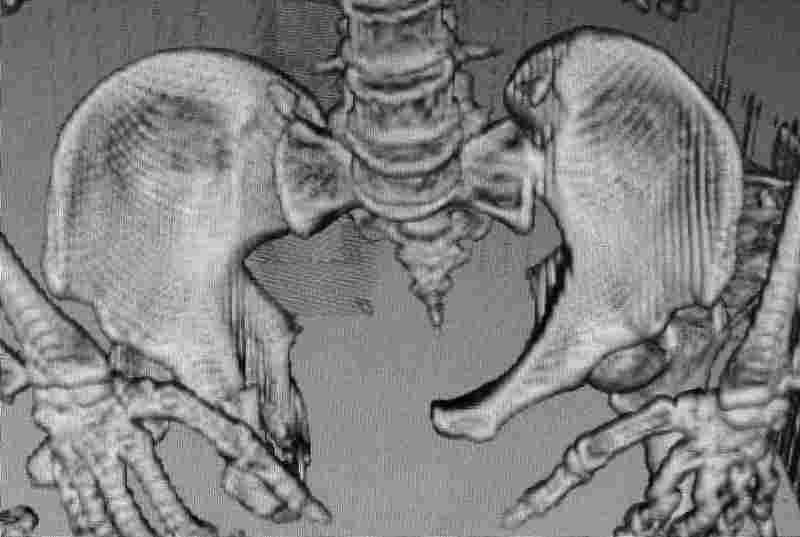

Коллеги, как и когда вы бы разрешили нагрузку в такой ситуации.

Молодой парень, без соматики. Сейчас чуть больше 2-х нед после операции,

швы сняты, мочится сам. Был тяжелый, после операции дней 10 пытался

выполнить лежа поперечный шпагат (успешно, так и лежал большей частью,

может быть из-за обширной гематомы промежности). Репозиция не

идеальная, но фиксация довольно надежная, за 2 нед ничего не

разъехалось". Сейчас пришел в ум. Когда, по-вашему, можно дать нагрузку,

и на какую ногу, или на обе? Или вообще подскажете

программу реабилитации.

PS Заранее извиняюсь за качество снимков, до не делали (body scan),

если не видно - то - полные разрывы КПС с двух сторон. после КТ

сломался. Неврологии вроде бы нет.